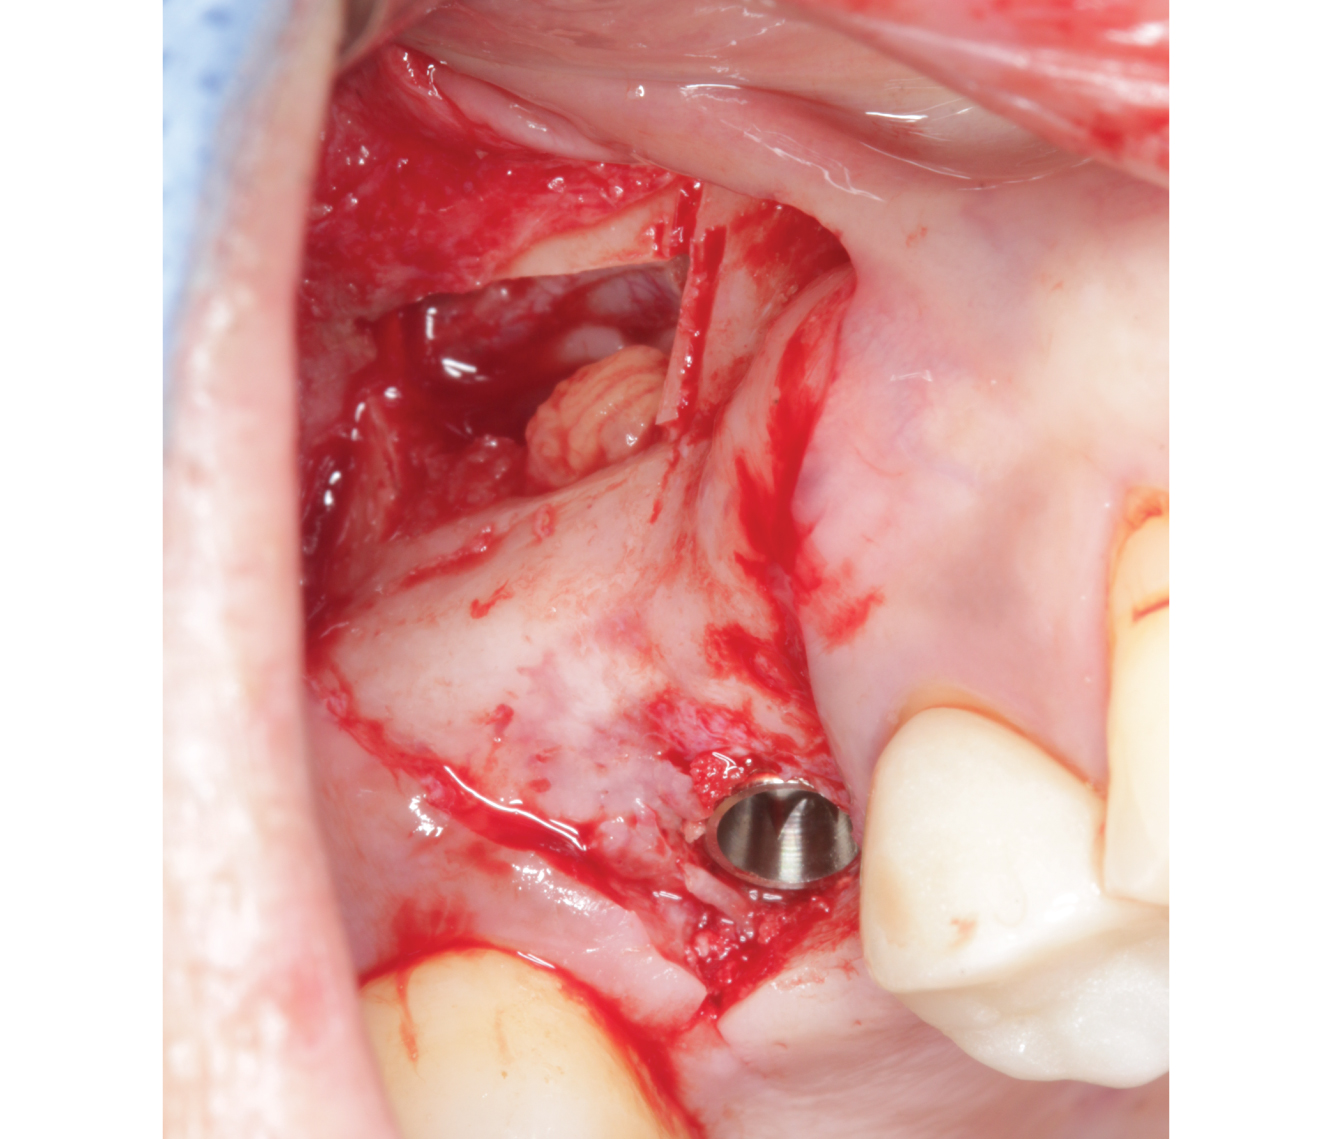

Director’s Clinical Cases

Director’s Clinical Cases